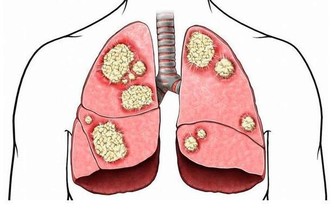

肥肉生濕生痰,還會加重脾虛和肺熱的症狀,在孩子感冒期間我們的飲食應該有所調整,不能再像平日里那麼多大魚大肉,這樣不但不會讓咳嗽痊癒,還會一直拖一直拖,咳嗽拖成支氣管炎就更難治癒了。